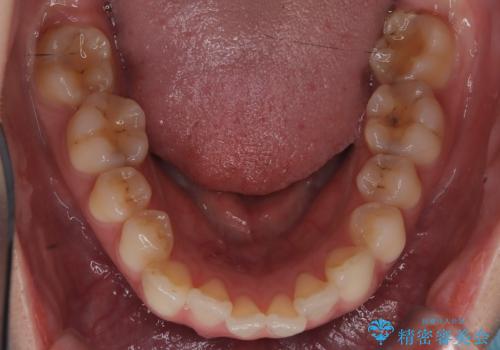

- 歯並びの乱れを改善したいと来院されました。精密検査の結果、犬歯を奥へ動かすことで、より美しい口元と安定した咬み合わせが得られると診断。患者様のご希望から、目立ちにくい審美ワイヤー矯正を採用し、効率的な歯の移動のために**リンガルアーチとTAD(矯正用アンカースクリュー)**を併用する計画を立てました。これにより、抜歯せずにスペースを確保し、犬歯をスムーズに遠心へ移動させます。

今回の矯正では、装置が目立たないよう透明なブラケットと白いワイヤーを使用。さらに、効率的な歯の移動のために、歯の裏側にリンガルアーチを設置しました。また、確実な奥歯の移動のために**TAD(矯正用アンカースクリュー)**を一時的に使用。これにより、犬歯を狙った位置へ正確に動かすことが可能に。目立ちにくい装置で快適に過ごしながら、理想的な歯並びと咬み合わせを獲得していただけました。